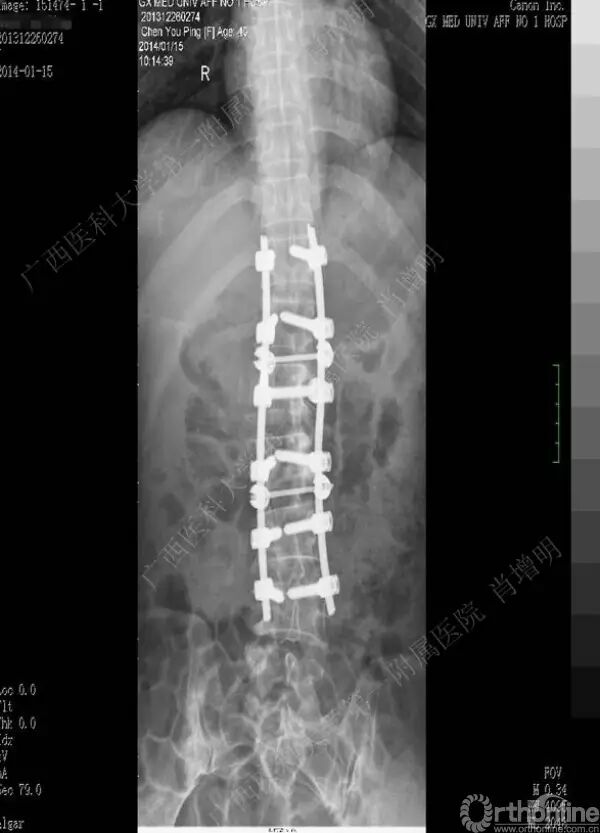

退变性脊柱侧凸是由于椎间盘退变后继发小关节退变,椎管和神经根管容积变化以及脊柱失稳,畸形等病理改变,以疼痛和神经压迫症状为主要表现的常见疾病。

退变性脊柱侧凸多发于50岁以上的中老年群体,是现代常见的老年疾病。多年来,针对该病的临床研究一直没有停步,广西医科大学第一附属医院肖增明教授细致地介绍了该病的诊疗进展。